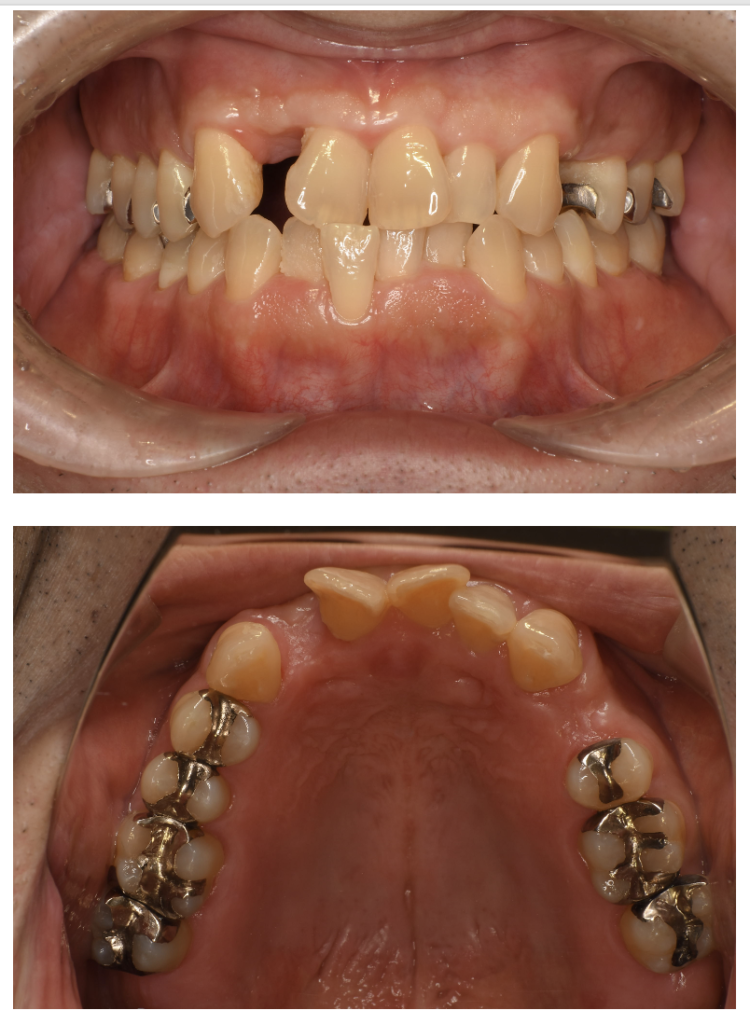

インプラント 14 N0.89

Before

After

| 備考 | 院長より 残すことが難しい状況になった歯を抜いて、インプラントを埋入しました。パンが食べられるようになった、お口の中に頬張って食べられるようになったと喜んでいらっしゃいます。 インプラント(人工歯根)と被せ(フルジルコニアCr)はネジで連結してあり必要に応じて外してチェックできるようになっています。 写真ではメンテナンス時でネジ穴が見える状態になっています。通常はネジ穴はプラスティックで蓋をして見えない状態になっています。 |